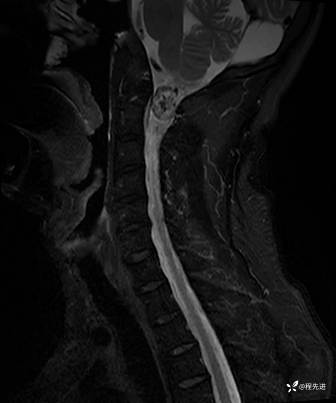

T2: